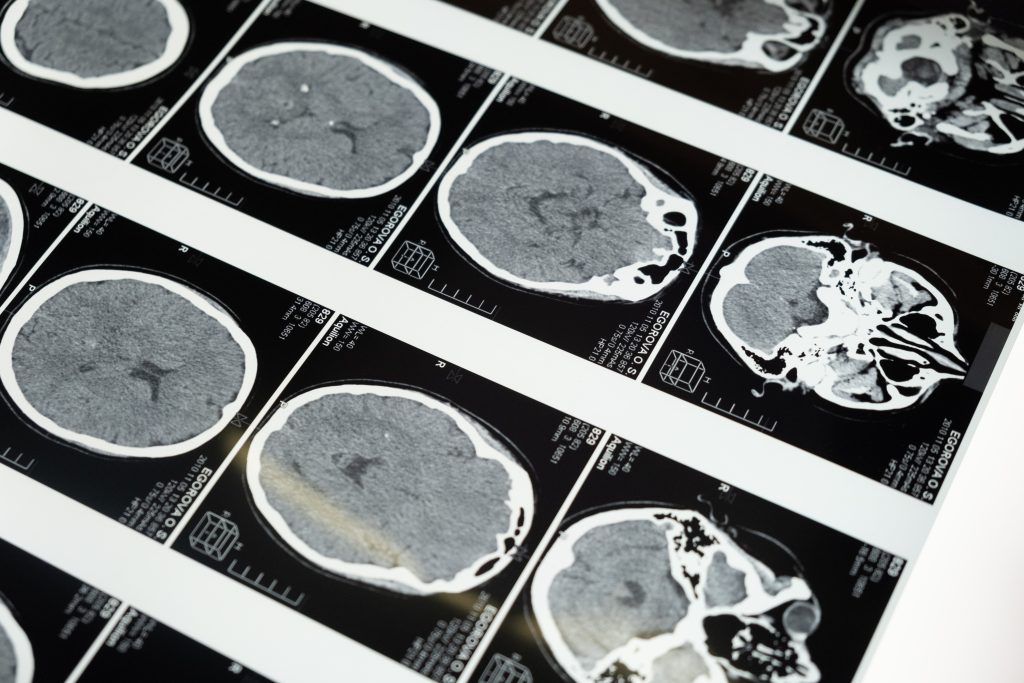

Ainda não se sabe as causas das doenças raras, mas estudos demonstram que 80% de todos os casos têm origem genética. Outros fatores envolvidos podem ser infecções bacterianas, virais, alérgicas ou condições ambientais. “Os exames de imagem podem ser utilizados nesses casos justamente porque conseguem mostrar a anatomia dos órgãos e identificar doenças raras ou complementar outros exames e o estágio em que cada uma se encontra”, esclarece Igor Santos, médico radiologista e superintendente de Inovação da Fundação Instituto de Pesquisa e Estudo de Diagnóstico por Imagem (FIDI). A instituição, gestora de serviços de diagnóstico por imagem da rede pública, realizou, entre 2019 e 2021, em hospitais públicos de São Paulo e Goiás, cerca de oito mil exames de imagem com o intuito de detectar doenças raras.